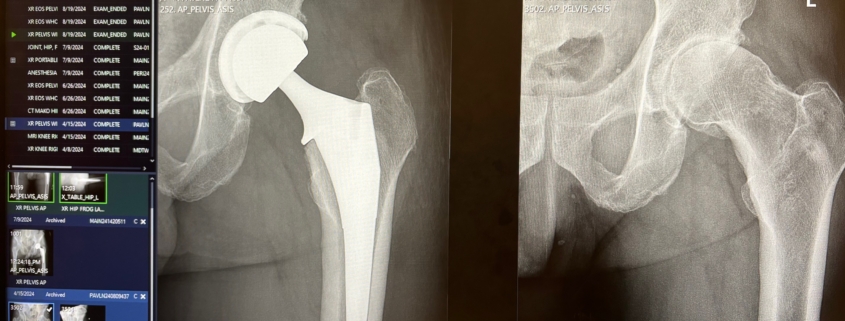

X-Ray of John Gleb’s Hip

Three months later, in early July, I had the surgical procedure done in New York City.